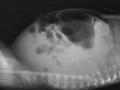

Hemorragia adrenal em recém nascido

A hemorragia da adrenal ocorre em até 3% dos recém nascidos, sendo a massa adrenal mais comum nesse grupo. Os principais fatores de risco são coagulopatias, hipóxia neonatal, sepse e trauma abdominal. A hemorragia é na adrenal direita em 80% dos casos. Nesse caso, o rim também apresentava nefrocalcinose.